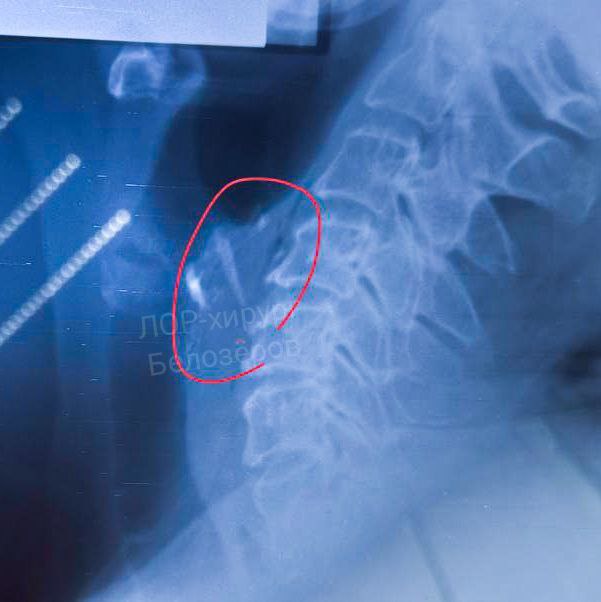

Нижегородец едва не умер из-за застрявшей в горле мясной кости

Осколок кости вонзился в гортань жителю Нижнего Новгород во время поедания мяса. Об этом сообщается в телеграм-канале главного редактора "Стационар-пресс" Алексея Никонова.

Заведующий лор-отделением городской больницы №35 Григорий Белозеров сообщил, что пациентом занимались молодой лор-врач Гюллу Нифтуллаева и бригада анестезиологов больницы.

Операция мужчине не понадобилась, так как удалось извлечь осколок до ухудшения ситуации и появления тяжелых осложнений.